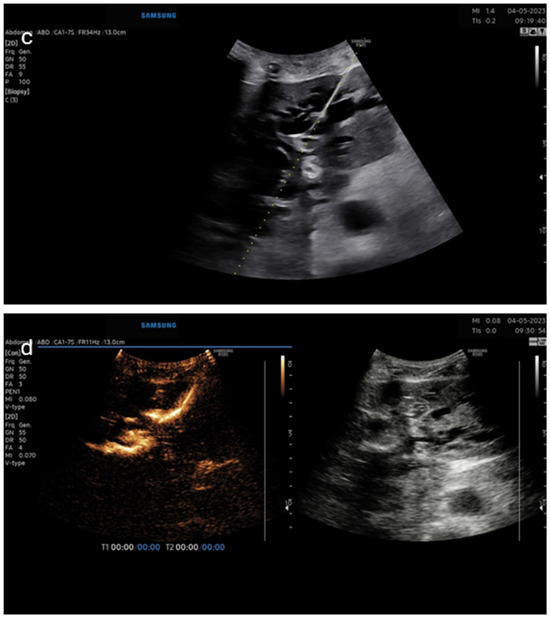

Figure 3. Panel (c)—B-mode image of left-sided puncture of the dilated bile ducts; panel (d)—(dual image—left CEUS image, right—B-mode) for confirmation of proper catheter position.

The second case was a patient with carcinoma of the antrum of the stomach with malignant infiltration of the pancreatic head and compression of the biliary tract (Figure 3). The biliary drainage was placed for palliative purposes. The pictures show an intracavitary injection of a diluted ultrasound contrast agent into a biliary drainage catheter inserted in the left liver lobe.